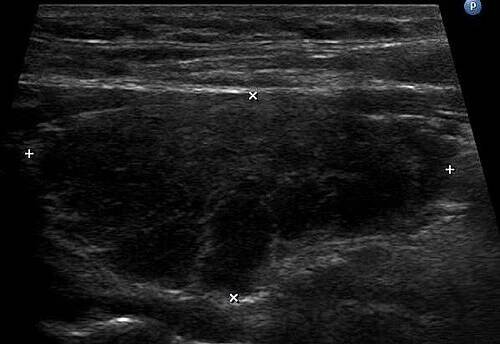

Hashimotova tyroiditida, také známá jako Hashimotova nemoc projevující se nejčastěji jako chronická autoimunitní tyroiditida (chronický zánět štítné žlázy), je autoimunitní onemocnění. Při tomto onemocnění dochází k napadání buněk štítné žlázy vlastním imunitním systémem. Jedná se o multifaktoriální onemocnění,…

Autoimunitní thyreoiditida (chronická lymfocytární tyreoiditida) je onemocnění štítné žlázy, které se u pacientů s diabetem mellitem 1. typu vyskytuje častěji než u běžné populace.

Toto autoimunitní onemocnění štítné žlázy je pojmenováno po Hakaru Hashimotovi, který ho poprvé popsal, a jedná se o chronický zánět, který může mít dlouhodobé následky na zdraví.